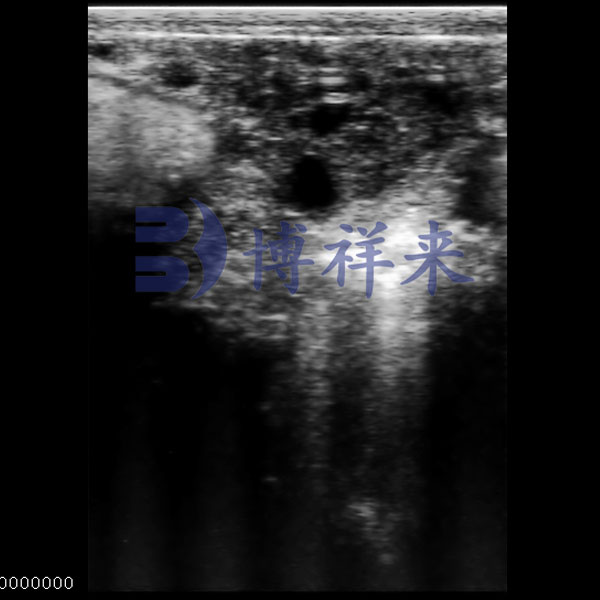

Bovine Pregnancy Ultrasound

● Depicts early gestational structures with clear contours.

● Stable contrast highlights fluid-filled zones.

● Outlines embryo–uterus spatial relation.

● Supports pregnancy stage evaluation.